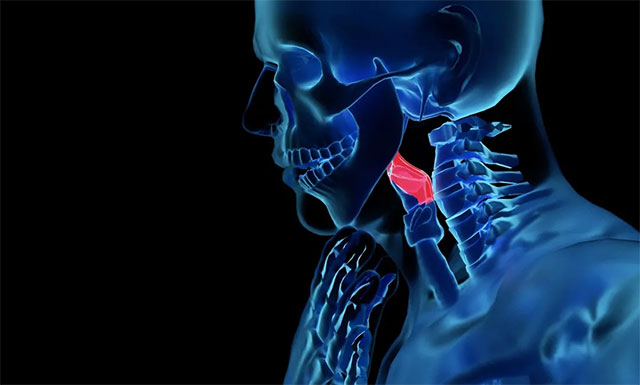

喉,是人体呼吸道的起始部位,除了承担着呼吸和发音两大基本功能外,还起着保护作用——当人们进食时,喉部“大门”(会厌软骨)关闭,避免食物落入喉腔引发窒息,即使不慎有“漏网之鱼”,喉也可以通过咳嗽反射使食物排出;当人们呼吸时,喉部“大门”(会厌软骨)打开,新鲜空气顺着喉腔进入肺部。喉癌就是发生在喉部的恶性肿瘤。喉癌在头颈肿瘤家族中比较常见,排在第三位,发病率2.1/10万,发病年龄多在40-60岁,多发于中年男性。

上海蓝十字脑科医院肿瘤科(放疗)王晓东主任介绍,喉癌是一种“狡猾”的疾病,起病往往“悄无声息”,且容易与咽喉炎相混淆,易被忽视。根据原发肿瘤发生部位的不同,喉癌早期可有以下典型症状: